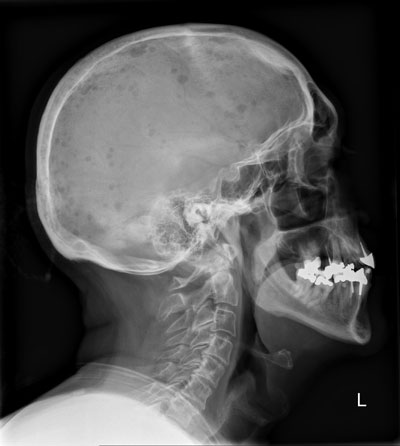

Ein 67-jähriger Patient kommt zu Ihnen mit diffusen Knochenschmerzen. Er klagt zudem über Müdigkeit, Abgeschlagenheit, Gewichtsverlust und Nachtschweiss.

Klinisch fällt eine Druck- und Klopfschmerzhaftigkeit des Skeletts v.a. entlang der Wirbelsäule und Hüfte auf. Mit blossem Auge sind sichtbare Deformierungen und Erhebungen im Bereich des Schädels erkennbar, woraufhin zunächst ein Schädelröntgen erfolgt.

Das Seitenbild des Schädels sehen Sie hier:

Schädel seitl.